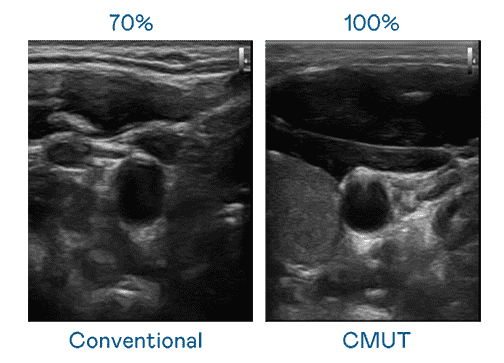

CMUT 技术是一种用电容式微机电元件来产生超音波讯号的技术。。。与传统 PZT 压电式技术相比,,,CMUT 频宽增加 30%,,,更宽频的超音波讯号让影像解析度大幅提升,,,是实现高影像品质医疗超音波扫描、、促进精准医疗发展的关键技术。。

大频宽带来超清晰影像

超音波影像的解析度高低,,首先取决于探头能发出的讯号频宽。。彩神vll CMUT 可提供高清晰的超音波讯号,,提供高频宽、、、高灵敏度、、、影像纹理细节更高的超音波影像,,协助医护人员缩短影像判读时间及利用精准的医疗影像进行诊断。。。。